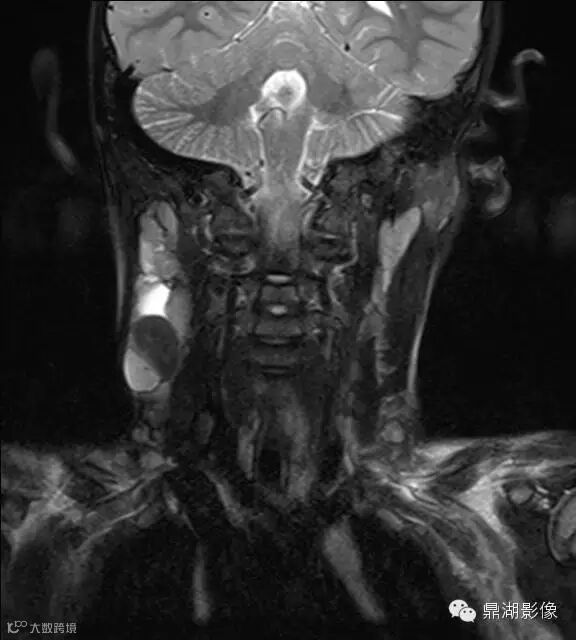

病史:男,5岁,发烧起病 39.5,咽痛,扁桃体II度,家属发现颈部肿块,质地硬,压痛。

上海儿童医院韩燕乔教授诊断:考虑淋巴结炎 ,可见杯状分层,液液平

出院临床诊断:上呼吸道支原体感染,淋巴结炎

颌面部淋巴结炎是临床较常见的一种疾病,尤其是小孩发病率更高。经常发生在颌下及颏下,有时也发生在耳后,面部和颈侧。颌面部的淋巴结炎大多是以下原因引起感染。上呼吸道感染,如扁桃体炎、咽炎、鼻炎、鼻窦炎等;口腔感染,如牙龈炎、牙周炎、口腔溃疡、冠周炎等;皮肤损伤与感染,如头面部皮肤化脓性伤口、湿疹感染、疖肿等。以上各种感染的细菌均可以随着淋巴液的循环,流经颌面部的相应淋巴结,使相应部位的淋巴结遭受细菌的侵犯,引起淋巴结的炎症。